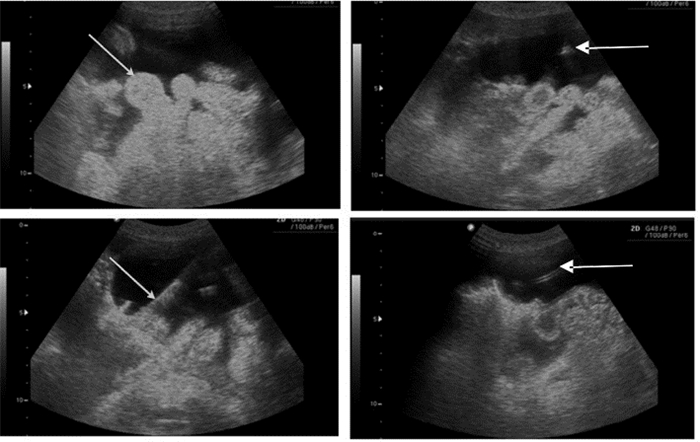

(4)超声引导下腹腔穿刺术( ultrasound of paracentesis) 大量腹水引起腹部不适,如伴发腹水感染或影响呼吸或静脉回流,则危及生命。床旁超声指导穿刺抽液,可减少医源性损伤。

超声探头多选择腹部探头。超声定位并标记腹腔穿刺点,一般选择“反麦氏点”或腹水最深处,且避开腹内脏器、如漂浮的肠管、膀胱、肝脾等。整个操作过程中都在超声引导下进行。针尖及导丝一旦进入无回声的液体区时就可表现为强回声影(图 44)。

|

| 图 44 腹水中漂浮的肠袢(左上),箭头所示;穿刺针尖(右上);置入导丝(左下);置入导管(右下) |